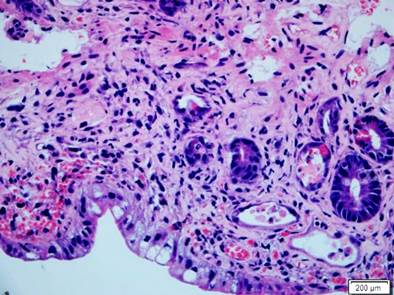

Se presenta el caso de un paciente masculino de 17 años con diagnóstico de linfoma linfoblástico T, que recibió inicialmente terapia de inducción y reinducción con protocolo GRAALL Lysa (citarabina + idarrubicina) con la que se logró la remisión de su enfermedad. Fue llevado a trasplante haploidéntico de progenitores hematopoyéticos con su padre como donante. Durante el proceso de trasplante desarrolló exantema macular difuso, de predominio en las extremidades. La biopsia de piel confirmó el diagnóstico de EICH aguda con compromiso cutáneo grado 3/4. Al día 32 del trasplante comenzó a presentar fiebre, dolor abdominal en el hipogastrio y ambas fosas ilíacas, además de deposiciones líquidas sin moco ni sangre. La tomografía axial computarizada (TAC) de abdomen documentó cambios inflamatorios de la región ileocecal y signos de ileítis terminal, razón por la cual se solicitaron estudios endoscópicos y en la EGD se encontró eritema plano en parches en el estómago, sin cambios inflamatorios en el duodeno. En la colonoscopia se halló mucosa del íleon congestiva con múltiples úlceras, superficiales, irregulares, de bordes planos y superficie lisa; además, en todos los trayectos colónicos incluyendo el recto se evidenciaron pequeñas úlceras puntiformes con fibrina en el centro y bordes planos congestivos (Figura 4). El estudio histopatológico confirmó el diagnóstico de EICH aguda en el íleon grado 3/4, colon derecho 1/4, colon izquierdo 3/4 y recto 4/4 (Figuras 5 y 6). La inmunohistoquímica (IHQ) sobre estas muestras fue negativa para citomegalovirus (CMV).

Inicialmente, se brindó manejo con dosis altas de metilprednisolona con respuesta parcial, razón por la cual hacia el día 15 de la enfermedad se decidió llevar a control endoscópico, tanto con EGD, que no demostró ningún hallazgo relevante, como con colonoscopia, que evidenció inclusive un empeoramiento de los hallazgos en el íleon con esfacelación de la mucosa, atrofia difusa con ausencia de vellosidades, sin cambios sobre las ulceraciones en el colon, que se correlacionó en las biopsias con progresión de la EICH aguda a grado 4/4, pero además con positividad para CMV en la IHQ. Se inició el manejo con ganciclovir y se consideró entonces el uso de ruxolitinib como manejo de segunda línea para la EICH. A pesar de esto, la evolución clínica fue hacia el deterioro, con empeoramiento de compromiso hepático por EICH, anemización progresiva por sangrado digestivo, e inclusive se inició terapia de rescate con infliximab sin ninguna respuesta, lo que finalmente condujo al deceso del paciente después de 58 días de hospitalización.